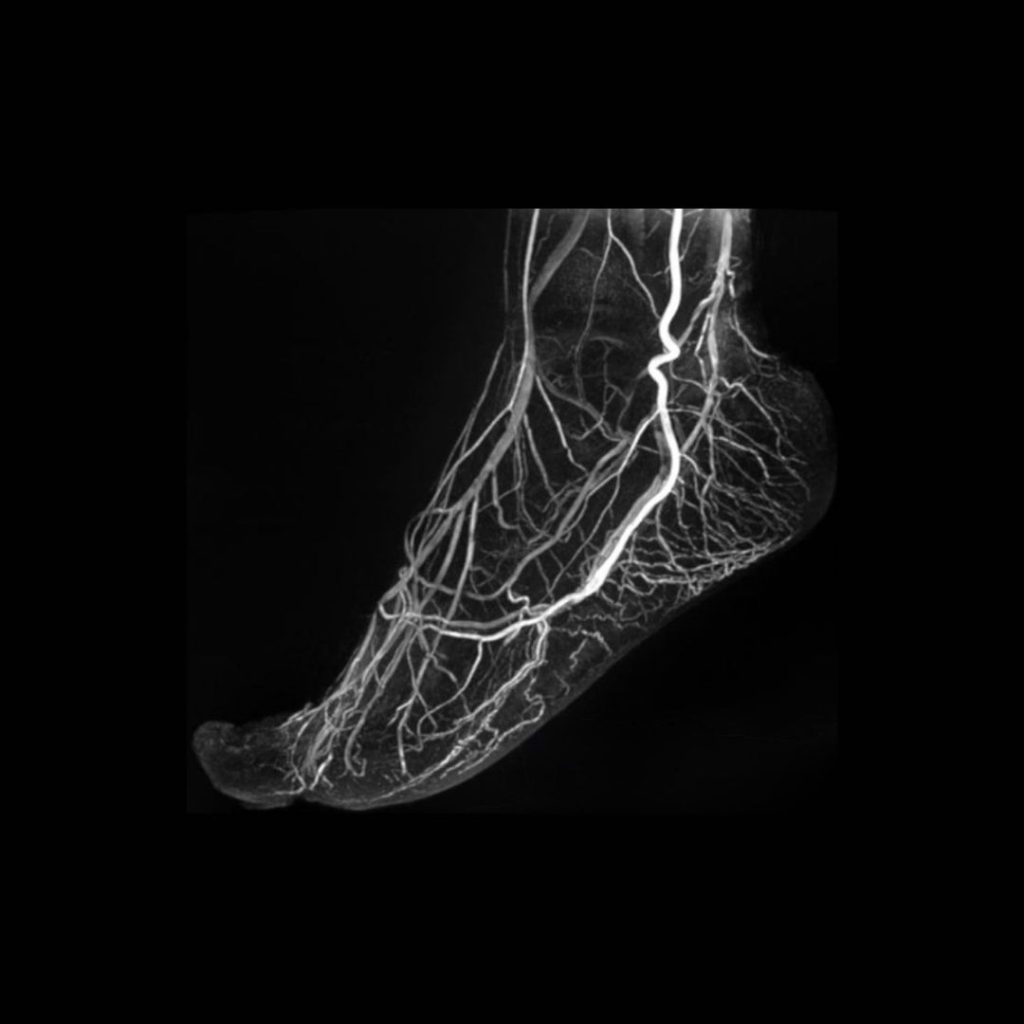

5 Tesla MR: Ayak Damarlarında Üstün Görüntüleme Gücü

Bu görüntü, 5 Tesla Manyetik Rezonans (MR) teknolojisinin ulaştığı olağanüstü detay seviyesini gösterir.

Yüksek manyetik alan gücü sayesinde, kontrast madde kullanılmadan bile ayak damarlarının en ince dallarına kadar net biçimde görüntülenmesi mümkündür.

5 Tesla MR;

- Üstün çözünürlük ile mikrovasküler yapıları belirginleştirir,

- Hızlı çekim süreleri ile hasta konforunu artırır,

- Niceliksel veri analizi sayesinde damar hastalıklarının erken tanısında önemli avantaj sağlar.

Bu ileri teknoloji, klasik MR sistemlerinin ötesine geçerek doku yapısını, kan akımını ve dolaşım bütünlüğünü en yüksek doğrulukla değerlendirir.

Sonuç: Daha net görüntüler, daha doğru tanılar, daha güvenli bir yaklaşım.

5 Tesla MR – Görüntülemede yeni bir çağ.